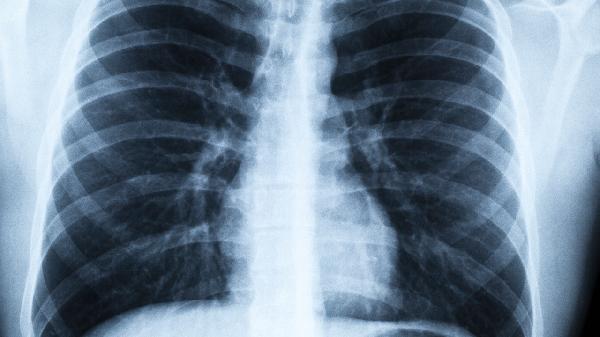

肺气肿中期属于疾病进展阶段,病情严重程度介于轻度与重度之间,主要表现有活动后气促、慢性咳嗽、反复呼吸道感染等症状。

中期肺气肿患者通常存在持续性呼吸困难,轻微活动即可诱发气促,可能伴有桶状胸、呼气延长等体征,肺功能检查显示中度气流受限。

该阶段肺功能持续下降概率较高,可能并发肺动脉高压、慢性呼吸衰竭,急性加重期住院需求显著增加,需警惕右心衰竭等继发损害。